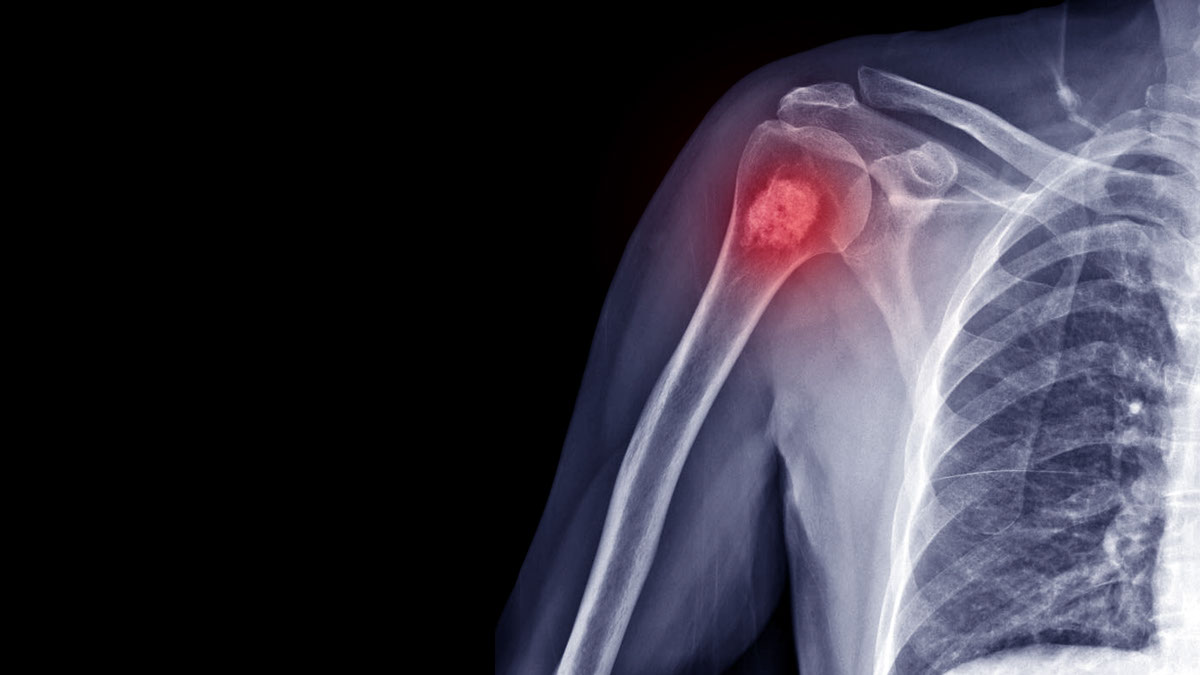

在這篇訪問中黃國全醫生和我們詳細解釋骨肉瘤 / 骨癌的各方各面,包括種類、徵狀、檢測方法,治療方法(特別是外科手術)、治療後的副作用和可以如何處理等。希望能夠令病人和照顧者有足夠的知識去和醫生及其他醫療團隊成員討論,從而面對和克服疾病。

黃:骨癌可分為原發性和繼發性。繼發性是指由其他部位的癌症 (如肺、乳房、前列腺等) 擴散至骨頭。理論上,任何骨頭也可受到影響。但一般影響大骨頭為主,如腰骨、盤骨或手腳骨。

大多骨肉瘤患者為小童或青少年,七成主要影響膝頭。患者會出現腳腫或疼痛,而且持續不退。由於小童及青少年處於成長階段,骨肉瘤可於個多至兩個月,大量侵蝕骨頭。軟骨肉瘤則影響老人居多,尤文氏肉瘤華人較少,同骨肉瘤一樣影響兒童居多。

原發性骨肉瘤可經過臨床檢驗和掃描,追查到那些是健康組織,那些是腫瘤。

黃: 受影響的骨頭會痛和腫。靜止時也覺得疼痛,甚至影響睡眠。由於近關節,活動幅度減少,影響走路。